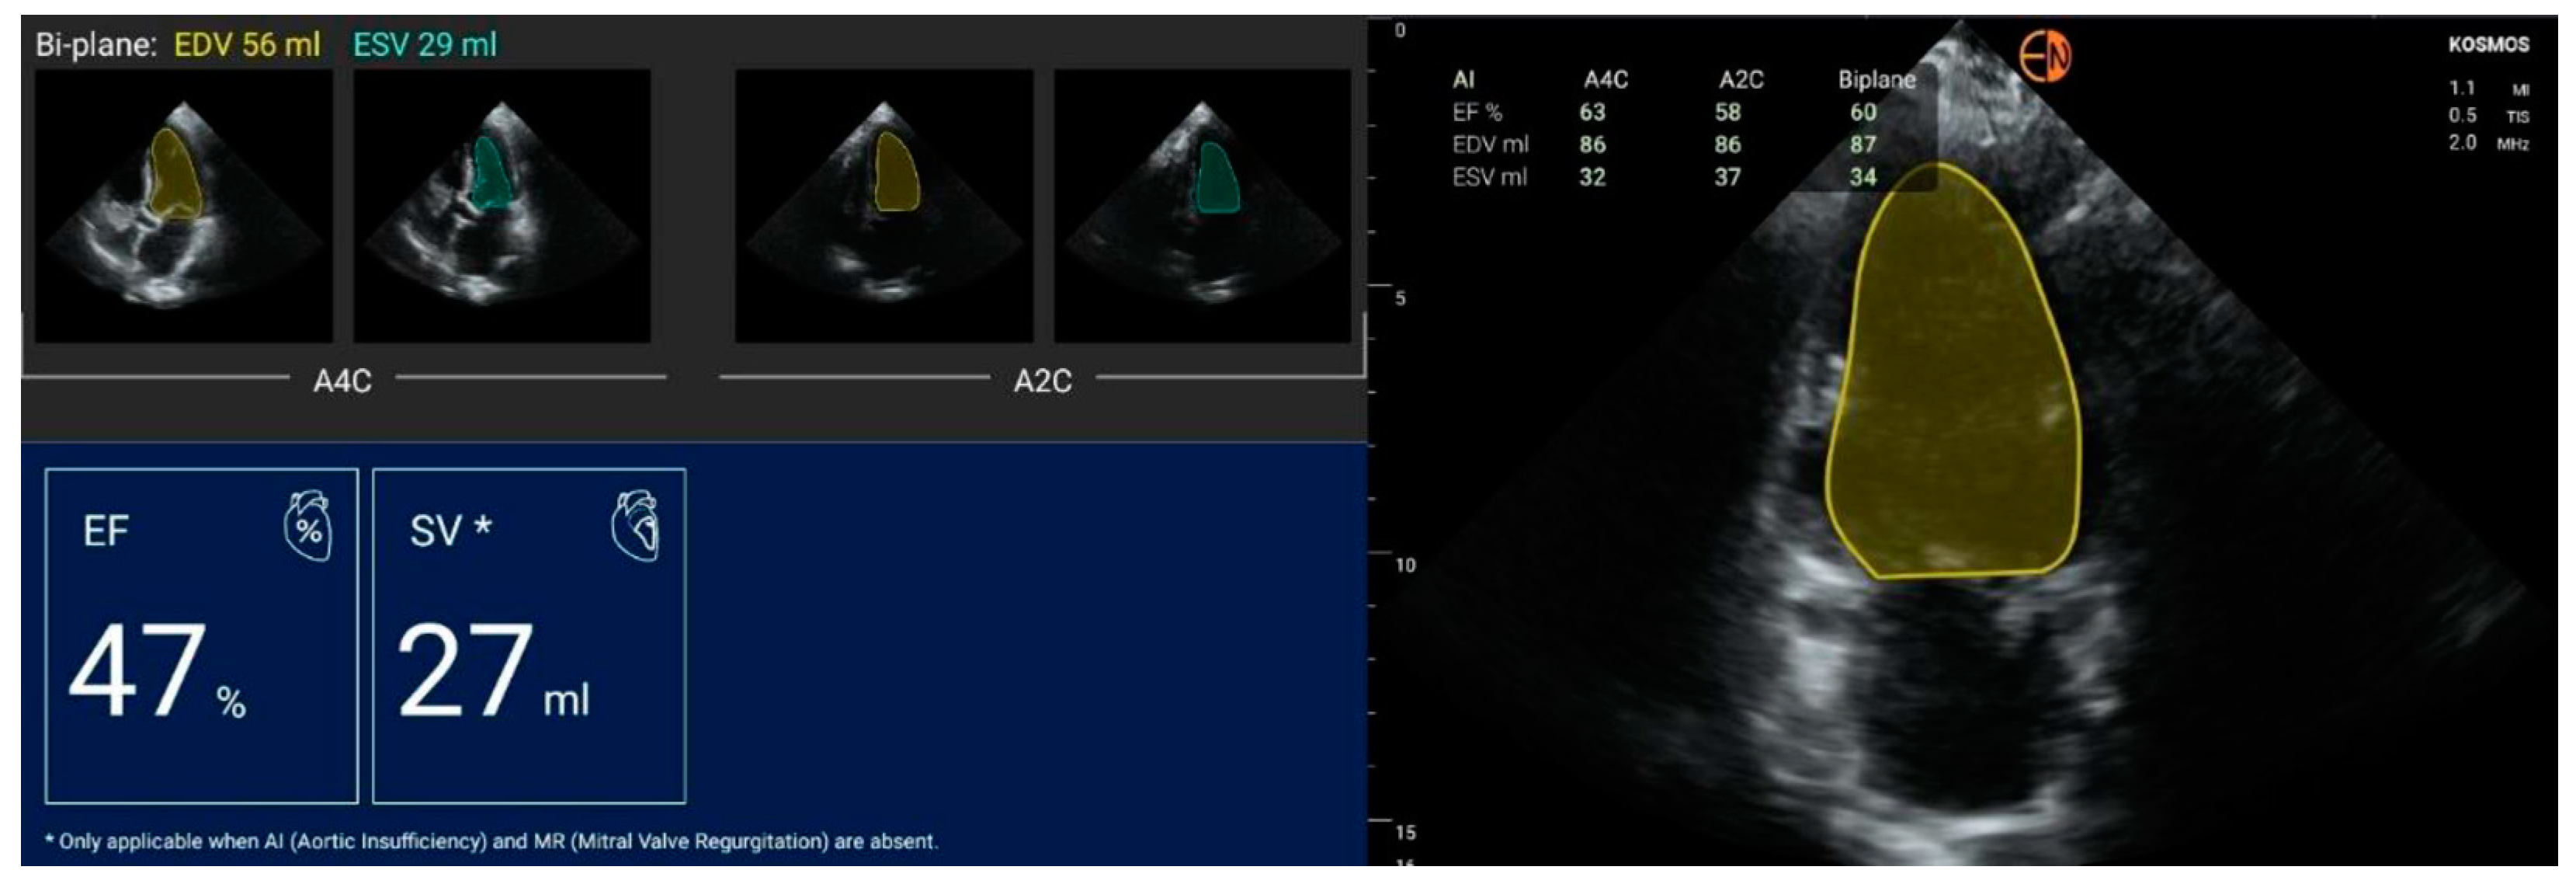

3.2. Measurements of Cardiovascular Structures

3.3. Valvular Stenosis and Regurgitation